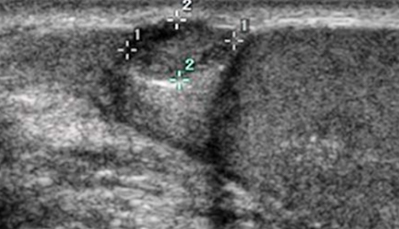

초음파 검사를 통해 음낭수종을

확진할 수 있으며 고환염,

부고환염, 탈장 등 다른 이상 유무를

확인할 수 있습니다.